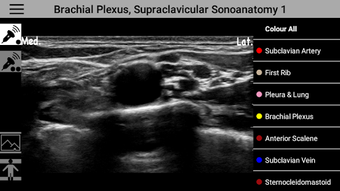

AnSo Anesthesia Sonoanatomyé um programa gratuito para Android, que pertence à categoria 'Medical' .

AnSo Anesthesia Sonoanatomy está disponível para Android 9.0 ou superior. A versão atual do programa é 2.1.47, e você pode executá-lo apenas em inglês.